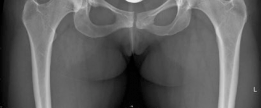

The radiographic evaluation of the dysplastic hip requires a highly standardized and rigorous protocol to accurately quantify the three-dimensional deformity. The initial assessment begins with a standing anteroposterior (AP) radiograph of the pelvis. In this patient, the AP view immediately reveals the hallmark signs of DDH: decreased anterolateral coverage of the femoral head and a broken Shenton line. The broken Shenton line—a step-off between the medial border of the femoral neck and the inferior border of the superior pubic ramus—indicates proximal and lateral migration of the femoral head due to structural instability. Furthermore, we observe an increased Tönnis angle (acetabular inclination) and a significantly reduced Lateral Center Edge Angle (LCEA) of Wiberg, confirming the diagnosis of severe lateral uncoverage.

The most critical functional radiograph in our preoperative workup is the AP Abduction view (often taken with the hip in 20-30 degrees of abduction and slight internal rotation). This view simulates the mechanical effect of a periacetabular osteotomy by effectively "rotating" the femoral head deeper into the acetabular dome. In this patient's case, the abduction view demonstrates excellent achievable congruency and congruity. The joint space becomes symmetric, and the femoral head centralizes perfectly within the socket. This is the ultimate litmus test for joint preservation: if the abduction view shows persistent incongruency or a "hinging" effect where the joint space narrows medially, a reorientation osteotomy may be contraindicated, as it would simply rotate a misshapen socket over a misshapen head, accelerating arthrosis.